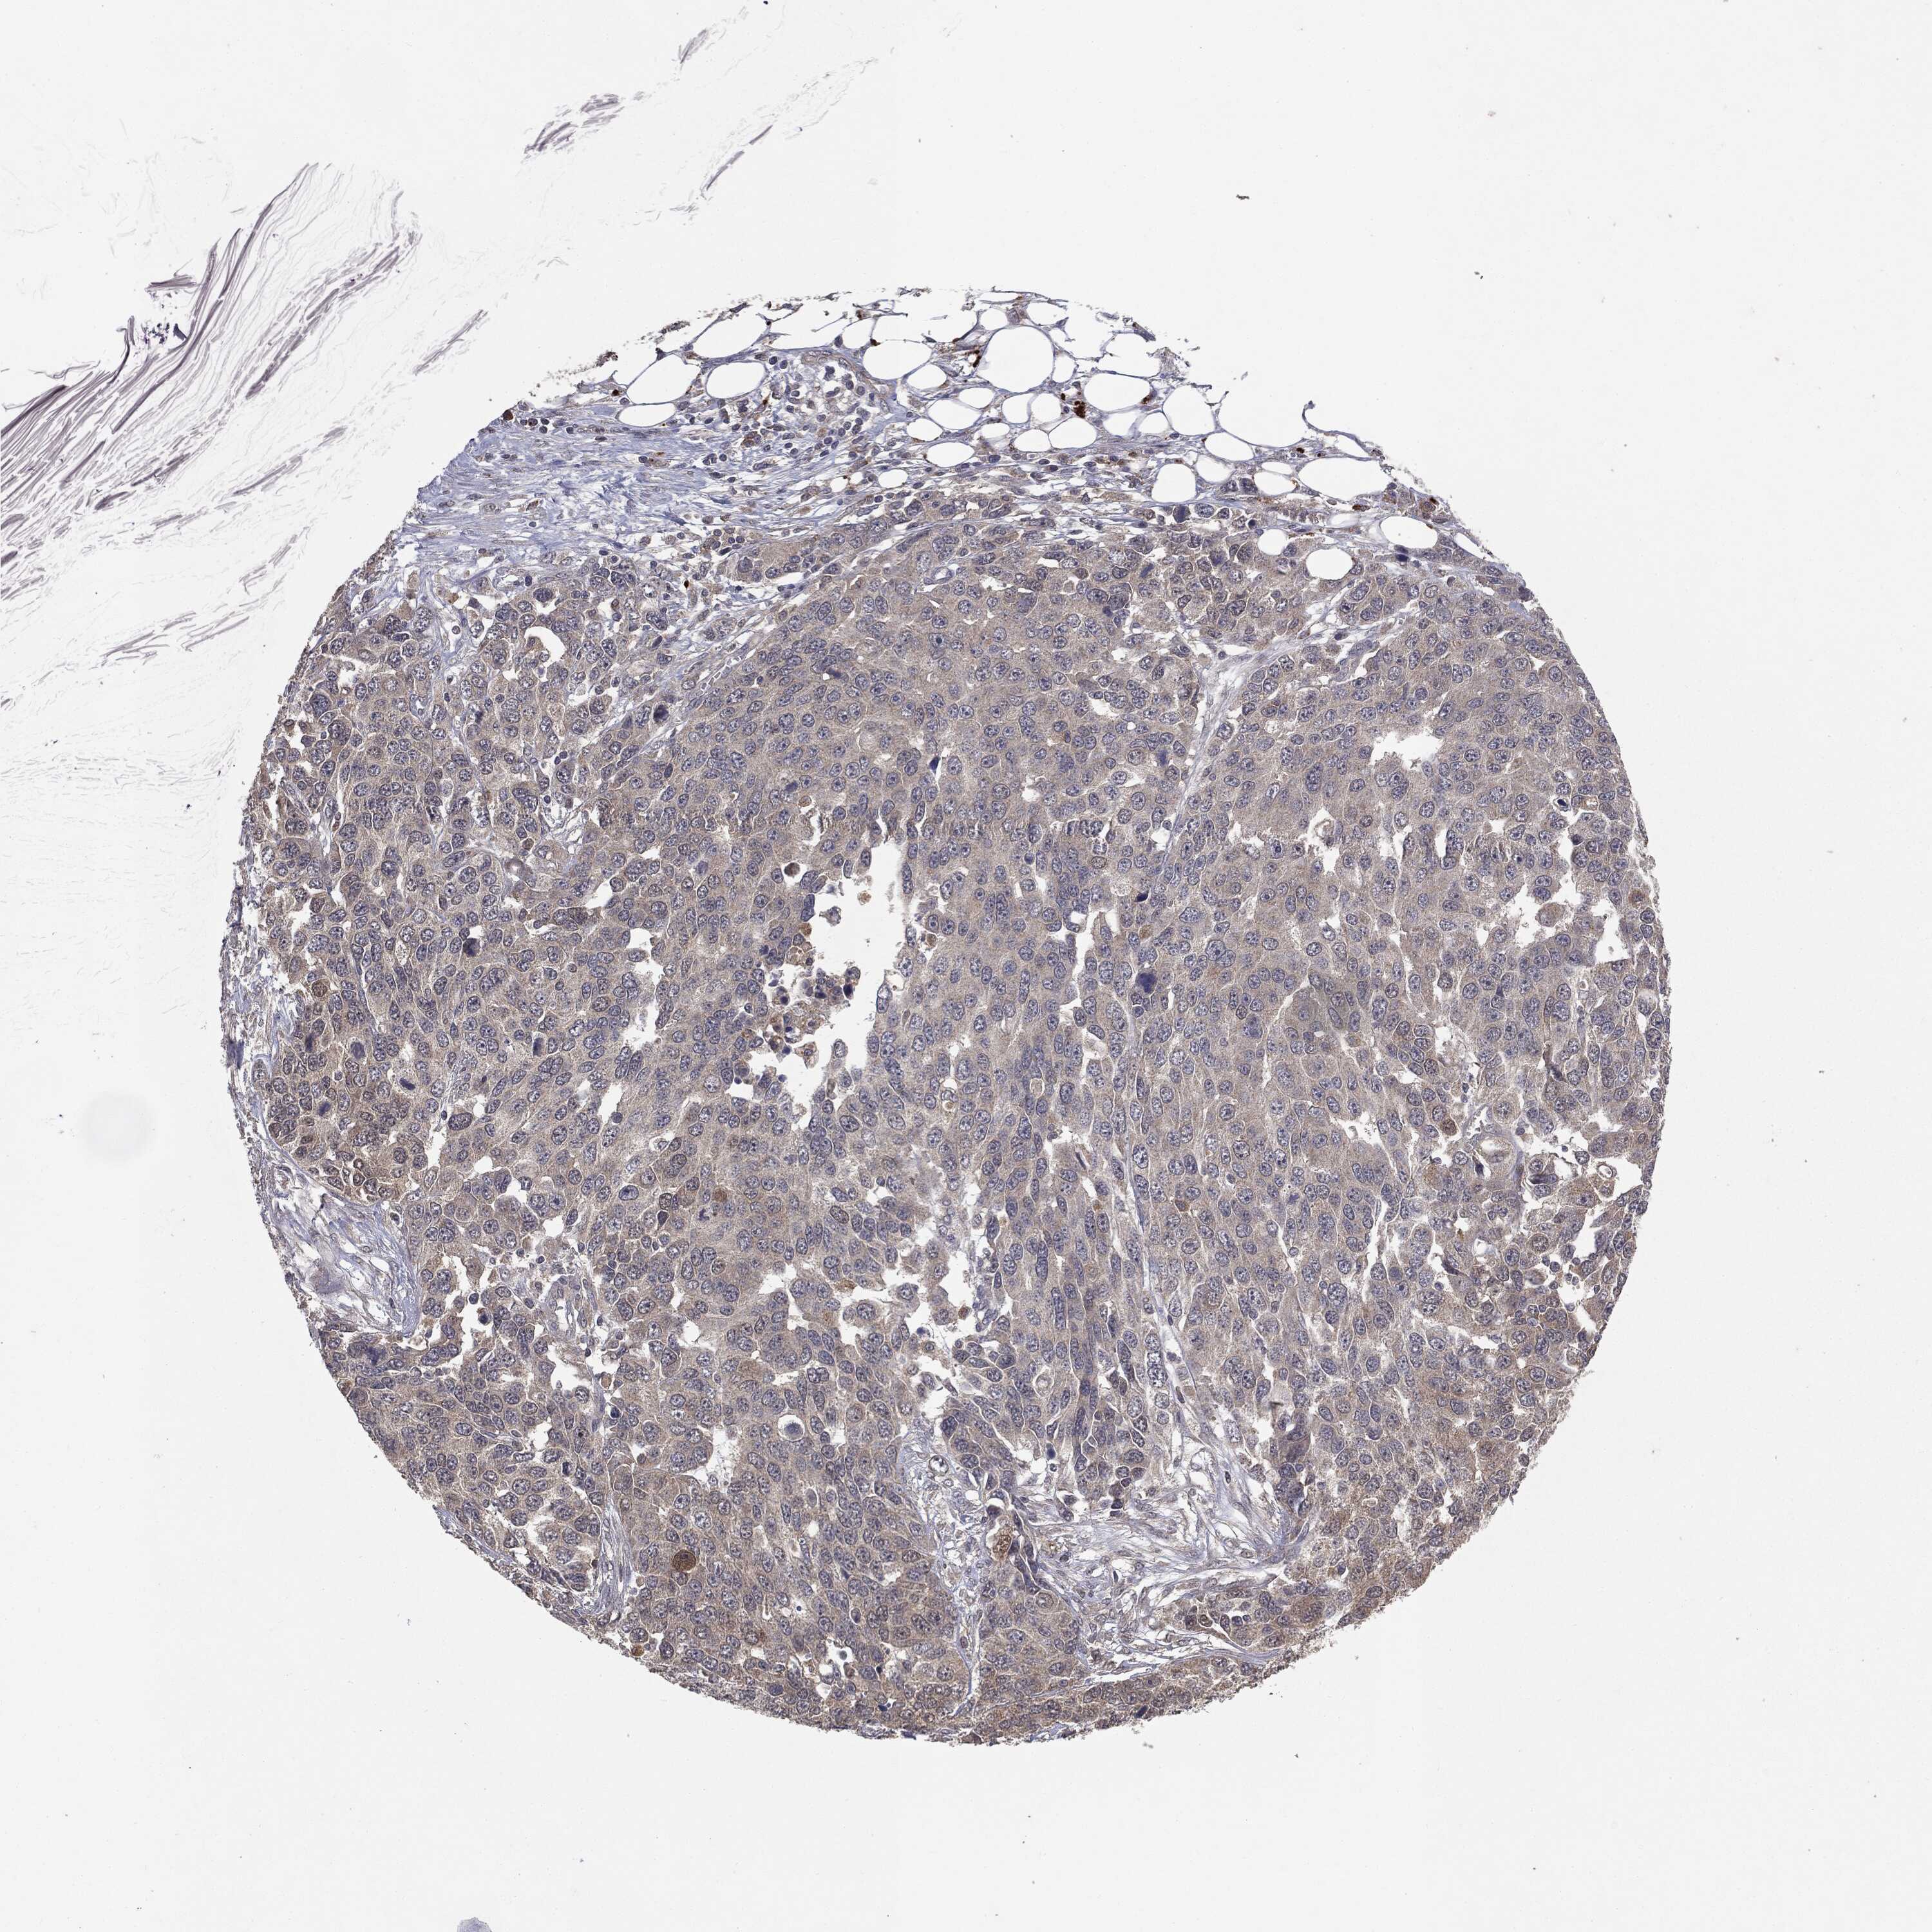

OVARIAN CANCER - Protein expressioni

A mouse-over function shows sample information and annotation data. Click on an image to view it in a full screen mode. Samples can be filtered based on level of antibody staining by selecting one or several of the following categories: high, medium, low and not detected. The assay and annotation is described here.

Note that samples used for immunohistochemistry by the Human Protein Atlas do not correspond to samples in the TCGA dataset.

Antibody stainingi

Antibody staining in the annotated cell types in the current human tissue is reported as not detected, low, medium, or high, based on conventional immunohistochemistry profiling in selected tissues. This score is based on the combination of the staining intensity and fraction of stained cells.

Each image is clickable and will lead to virtual microscopy that enables deeper exploration of all samples and also displays staining intensity scores, fraction scores and subcellular localization as well as patient and tissue information for each sample.

CAB080053

Cystadenocarcinoma, serous, NOS